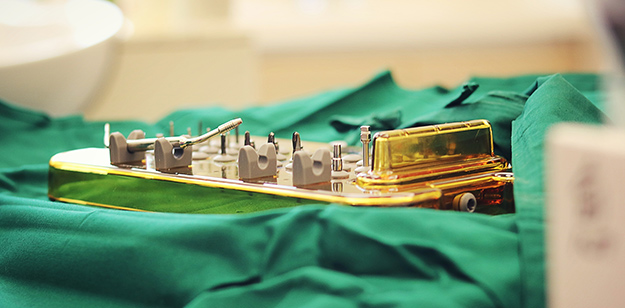

1、通过导板定位种植,即拔即种,术后即食

2、即使骨量严重萎缩,也可利用斜行植体等技术,避免植骨手术

3、植体需求少,可比传统种植所需植体少一半,口腔条件好的种植4颗植体可恢复半口牙齿

1、减少手术次数及缩短治疗周期

1、根据CT的3D成像,3D打印牙根。